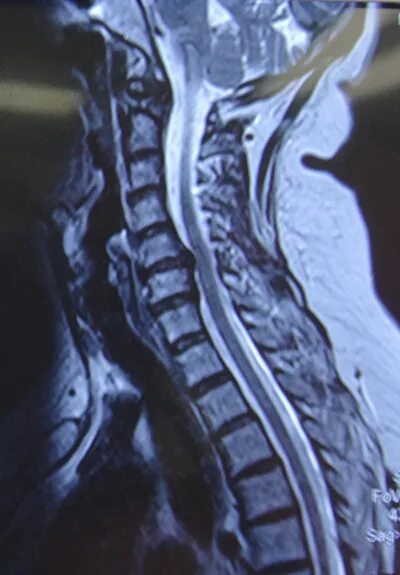

Протрузии дисков c6